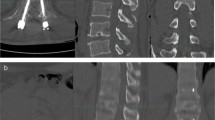

While single-energy CT is not able to remove bone trabeculations and to uncover subtle bone marrow attenuation changes, DECT allows for BME assessment [20, 49,50,51,52,53,54,55]. Moreover, its rapid acquisition time lends it favorably to emergency settings [46]. Several studies have been carried out to evaluate the diagnostic performance of VNCa reconstructions to detect acute vertebral fractures [56,57,58]. BME detection has been qualitatively assessed by using color-coded images and quantitatively using region-of-interest-based measurements of bone marrow attenuation. When microfractures are present within the cancellous bone, bone marrow attenuation increases since its fatty content is replaced by edema and microhemorrhages. Color-coded VNCa reconstructions show good to excellent results for qualitative assessment of BME, either in terms of sensitivity (range 72–96%), specificity (range 70–100%), and accuracy (range: 90–99%) (Table 2).

Similarly, receiver operating characteristic curve analysis of bone marrow attenuation on VNCa datasets has also demonstrated excellent sensitivity, specificity, and accuracy, ranging 85–96%, 82–90%, and 85–91%, respectively, using cutoff values from -80 and -12 HU [46, 56,57,58].

DECT imaging has been introduced as an attractive alternative, especially due to VNCa imaging, which achieved promising results for the identification of early stages of intervertebral disc degeneration. Using a maximum CT value of 800 HU and a threshold of -200 HU, VNCa color-coded maps with mixed CT overlay have demonstrated the ability to detect different grades of the modified Pfirrmann classification, which is widely used for disc degeneration grading [61]. In particular, VNCa imaging is able to detect an increase in disc attenuation that positively correlates to dehydration of nucleus pulposus and in a loss of its proteoglycan and water content.

More advanced stages of intervertebral disc degeneration are characterized by disc height reduction, fissuration of the annulus fibrosus, and herniation of the nucleus polposus. Standard CT has shown moderate sensitivity and specificity for the detection of lumbar disk herniation, despite the improved results coming from new iterative reconstruction algorithms [34, 62, 63]. More recently, DECT has overcome the impaired contrast resolution of intervertebral discs by application of color-coded VNCa reconstructions (Fig. 3).

Spine dual-energy computed tomography. Standard grayscale series (a) shows typical findings of spondylarthrosis with vacuum phenomena in L3/L4 and L4/L5 intervertebral discs. Virtual non-calcium reconstruction with optimization for intervertebral disc analysis (b) can finely show the protrusion of lumbar discs (arrows), confirmed by magnetic resonance imaging T2-weighted sequence (c) (arrows). From Booz et al. [34]

Color-coded maps help distinguish small disc herniations from cerebrospinal fluid, with better sensitivity and specificity compared to standard CT, respectively of 91% and 92%, using MRI as a reference standard (Table 3) [34].